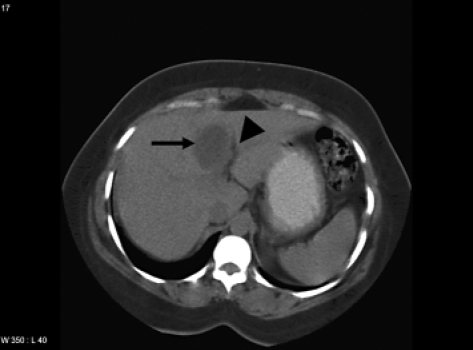

Representative CT Scan Image With Cyst In Liver Segment | Open-i

scan cyst

gastric ct submucosal cardia showing lesion scan figure tumor density abdominal layer arrow low